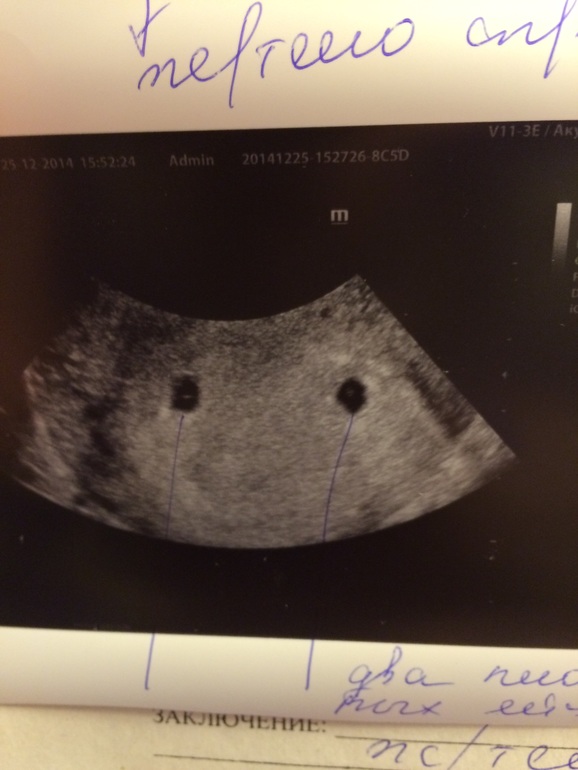

Неделю назад я у вас спрашивала,действительно ли видео вторую полоску на тесте,а сегодня после УЗИ могу точно сказать:"У нас получилось!")))☺️ И еще ого-го как получилось!) у нас двойня!)))

Двойное счастье